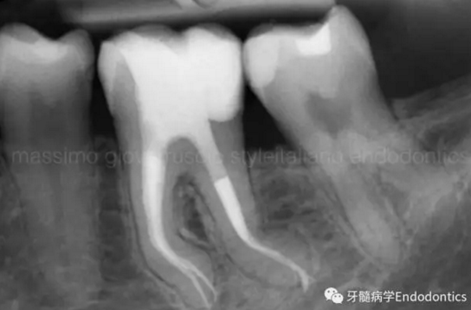

圖6.術(shù)后X線片顯示在根管機(jī)械預(yù)備后保留了原始的根管解剖形態(tài)結(jié)構(gòu)。冠方預(yù)敞和探查保證了對(duì)整個(gè)根管解剖形態(tài)結(jié)構(gòu)的保護(hù)。

圖11.術(shù)后X片顯示完成了根管的三維充填并很好地保留了復(fù)雜的解剖形態(tài)結(jié)構(gòu)。